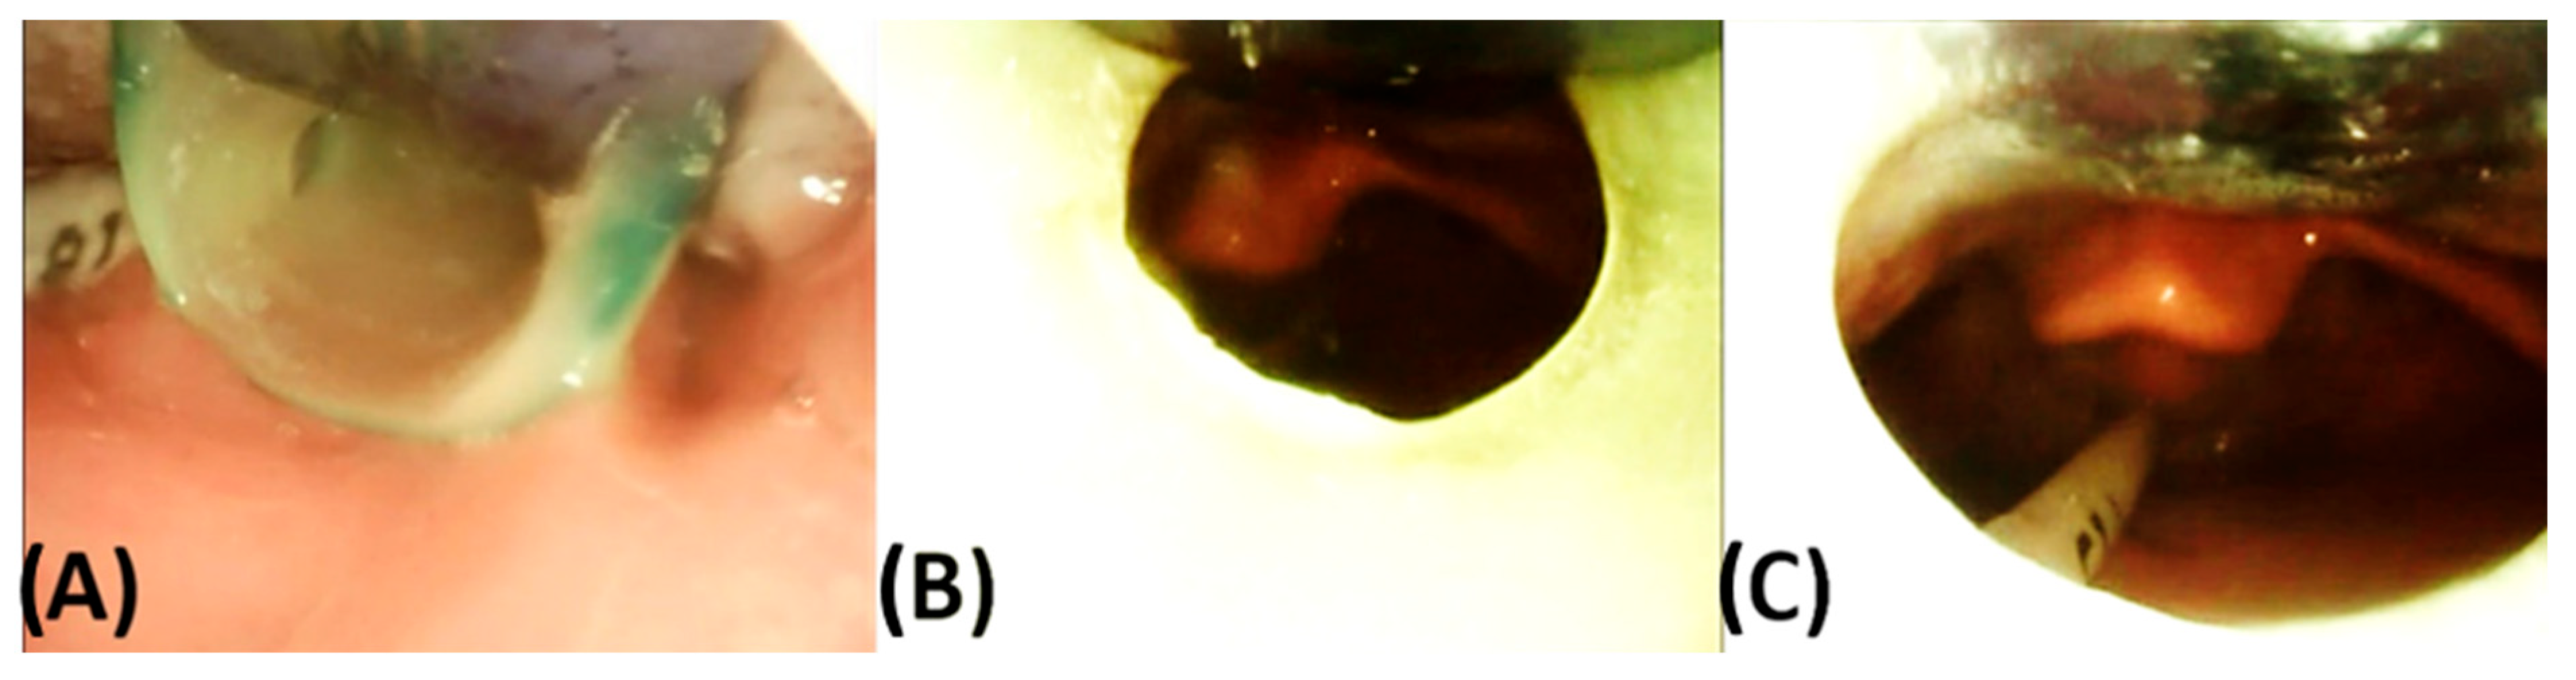

3.2. Endoscopic Exploration of the Prototypes